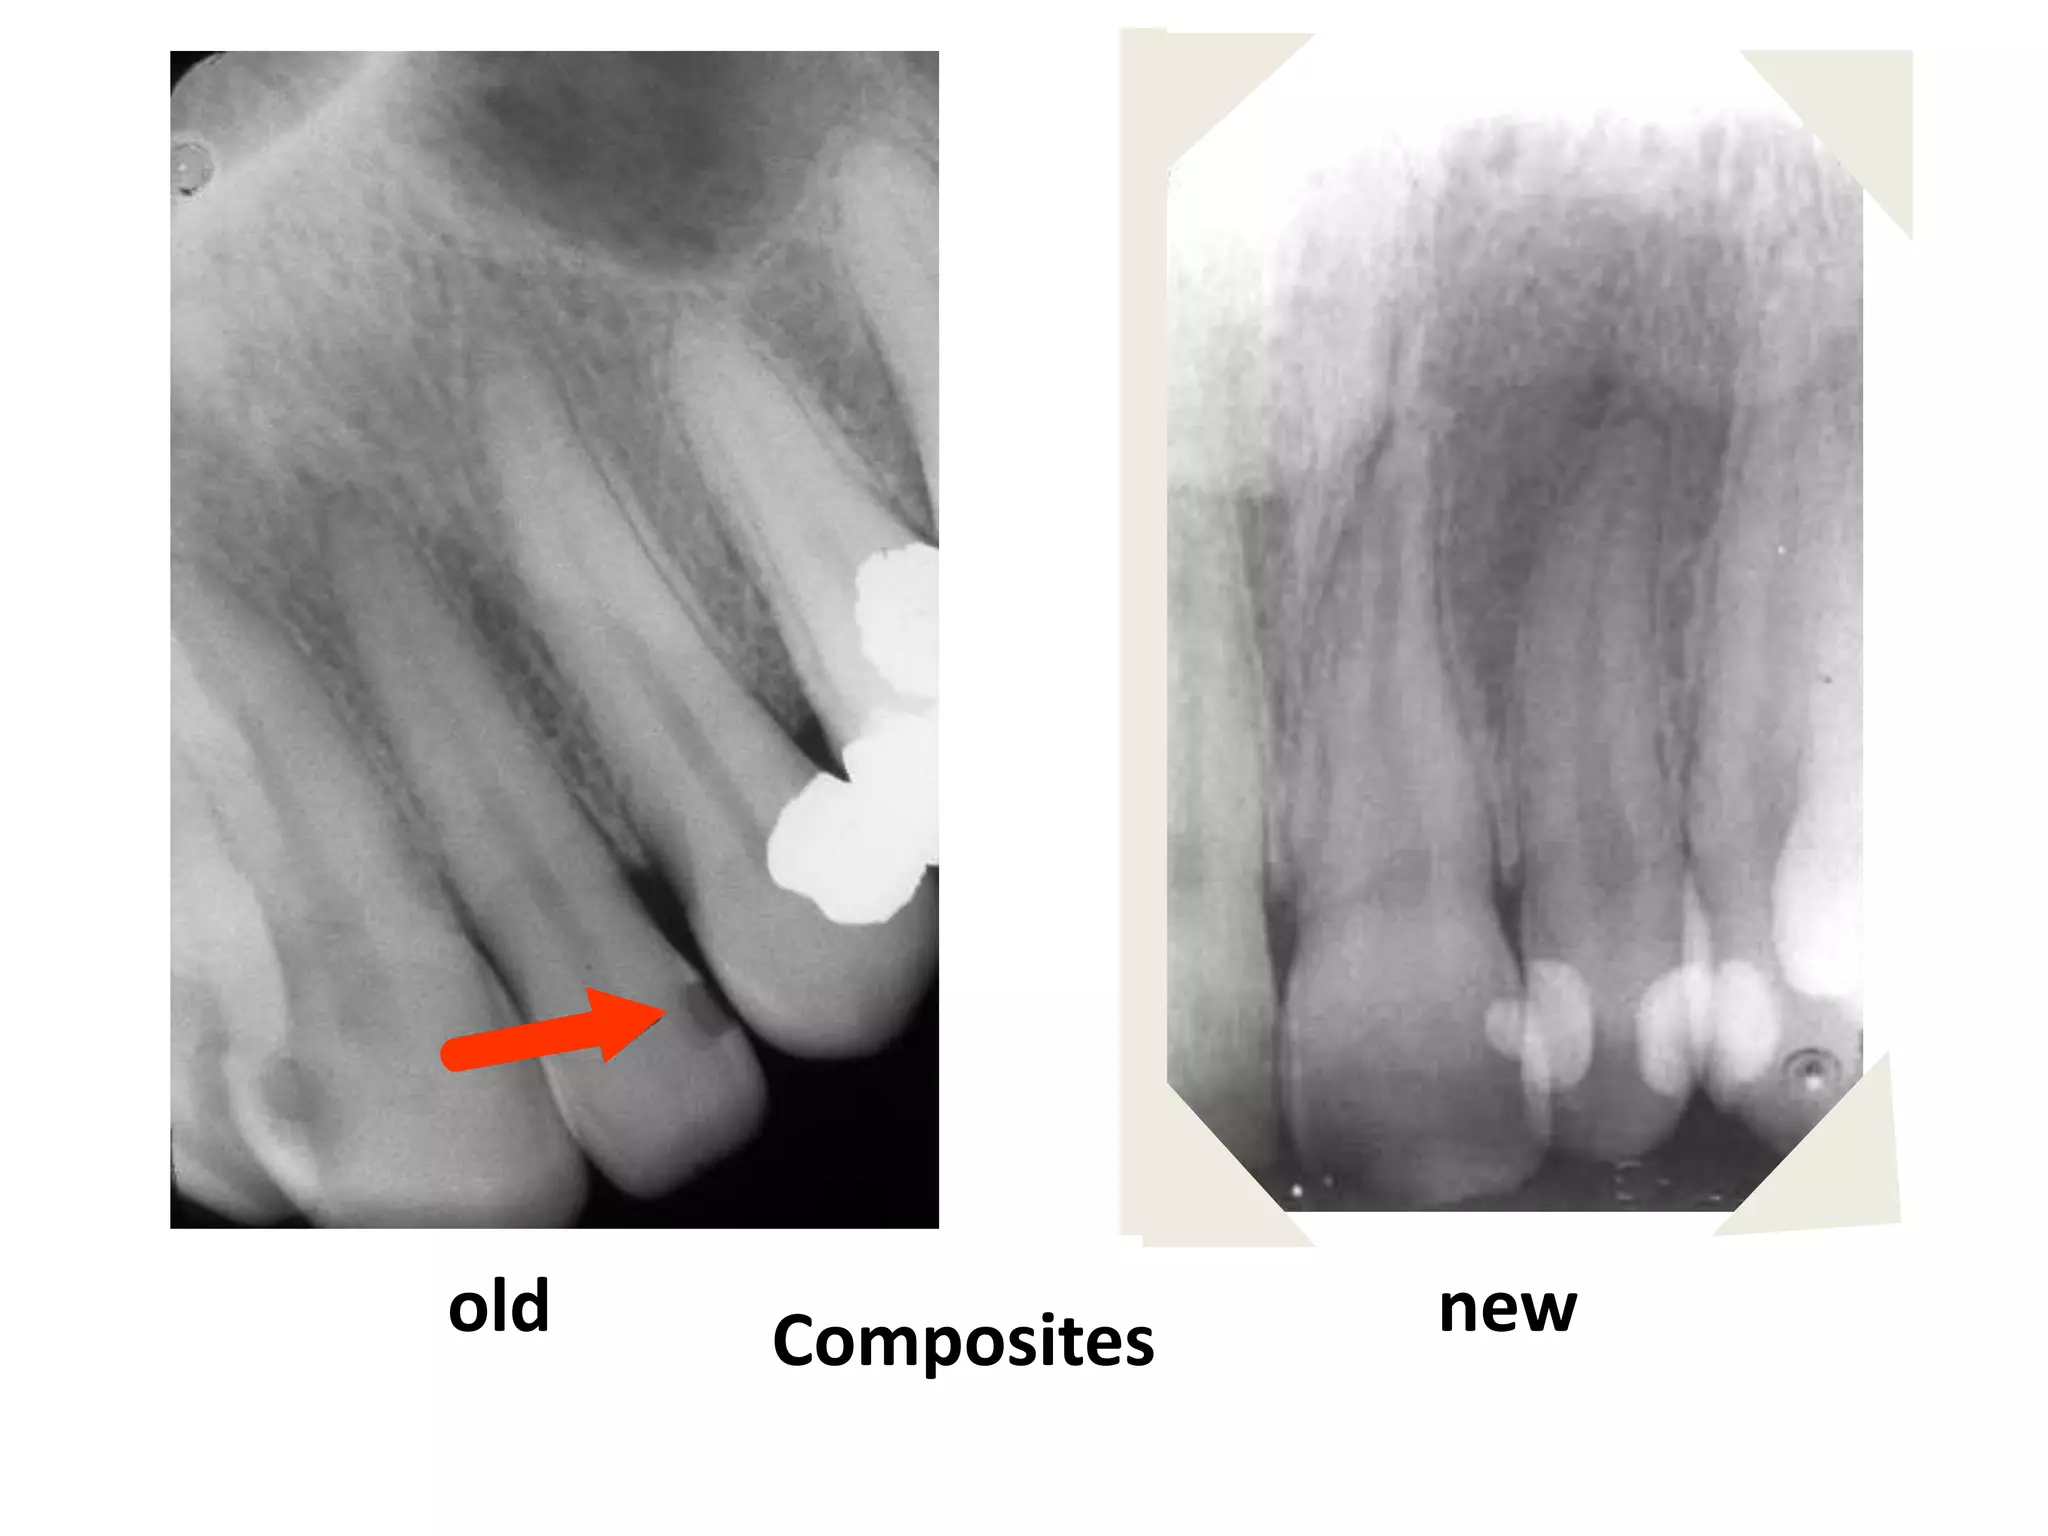

Restorative Materials

Radiopaque: Structures with higher object

density, such as amalgam, gold, silver

points, pins, gutta percha, porcelain.

Radiolucent: Structures with lower object

density, such as older composites and

bonding agents.

old   Composites   new